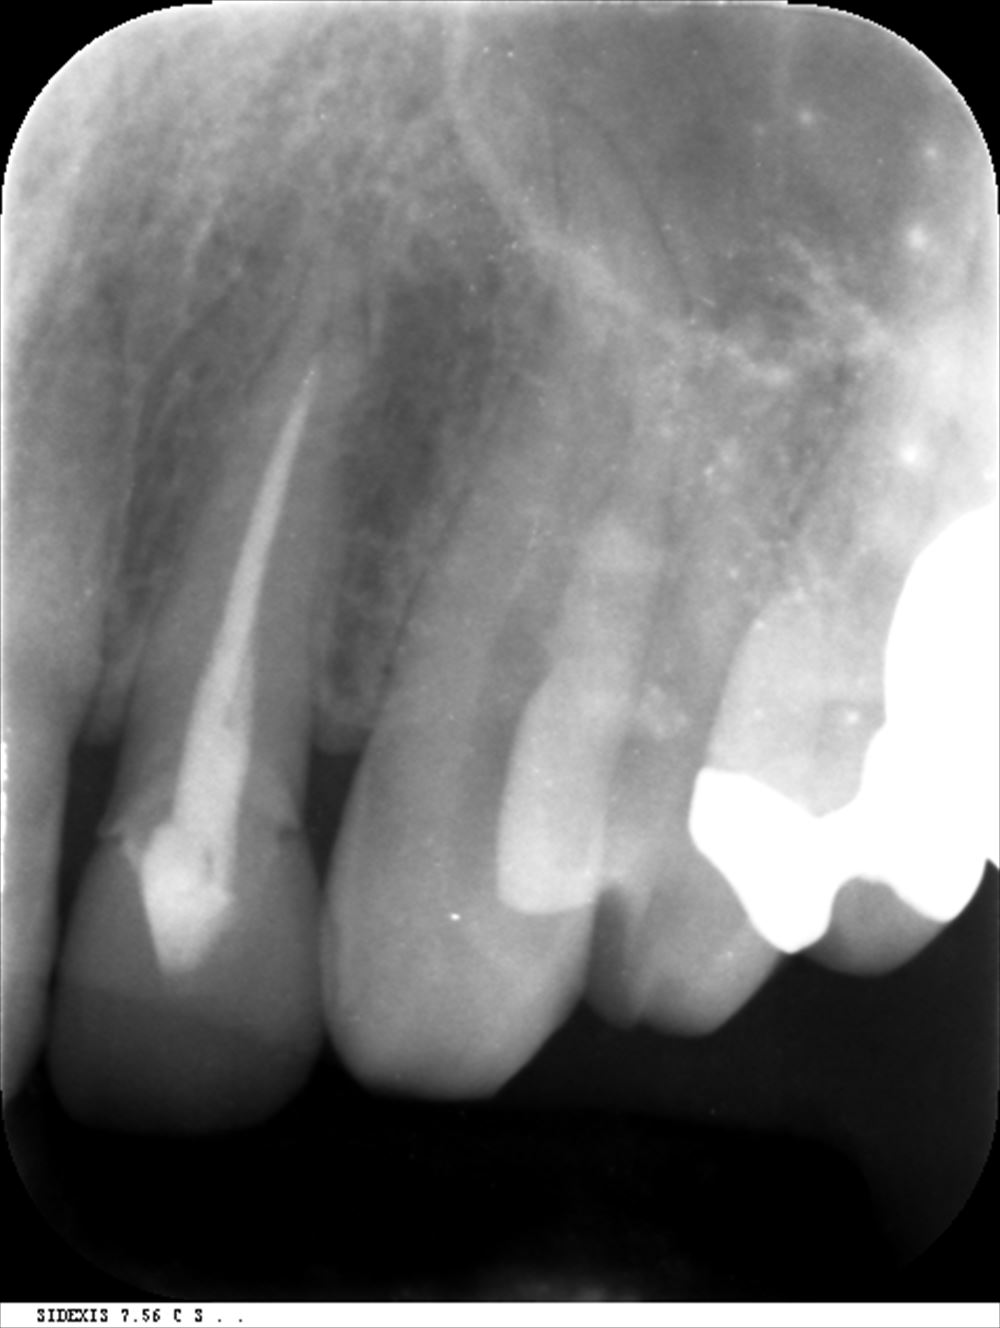

術前 根管充填が足りず感染がある。

術後 根の先まできっちり。

このケースは他院で説明がなく不安で当院に。歯科ドック後根管治療

根の先が見えるようにストレートラインアクセス

根管充填。3回で根管治療終了

術前

術後 症状も消えました!!